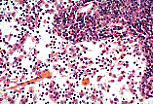

网状支架中可见大量巨噬细胞,它们在此行使吞噬功能(非特异性免疫)。

在这名矿工的炭末性淋巴结中,巨噬细胞内充满了炭尘颗粒。 |